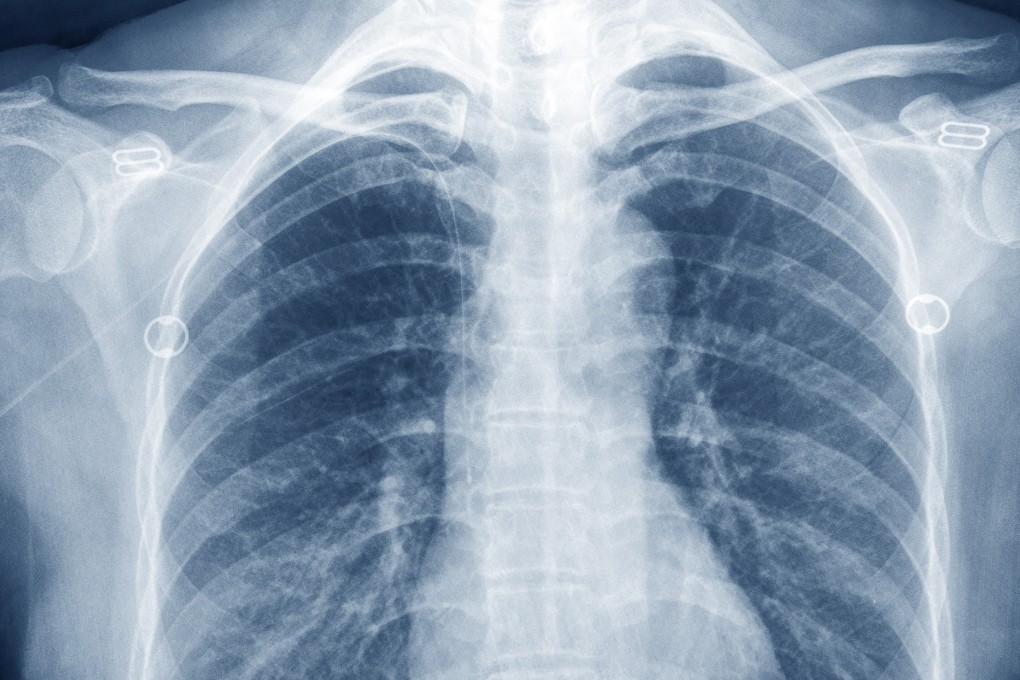

X-rays have shown promise in helping elderly patients to fight the coronavirus, according to a new study from the United States.

Ten Covid-19 patients who volunteered to have radiation therapy sent through their chests recovered much faster than those without, the researchers found.

The X-ray could be a “well-tolerated, inexpensive, and globally available Covid-19 treatment”, said the research team from Emory University in Atlanta, in a non-peer-reviewed paper posted on Medrxiv.org on Tuesday.

The median time of clinical recovery after the radiation therapy was three days, just a quarter of the time of those taking more common treatments, such as remdesivir and hydroxychloroquine.

The volunteers’ median age was 78, ranging from 43 to 104 years old. All of them were on ventilators with declining conditions. Most – 70 per cent – were African Americans.